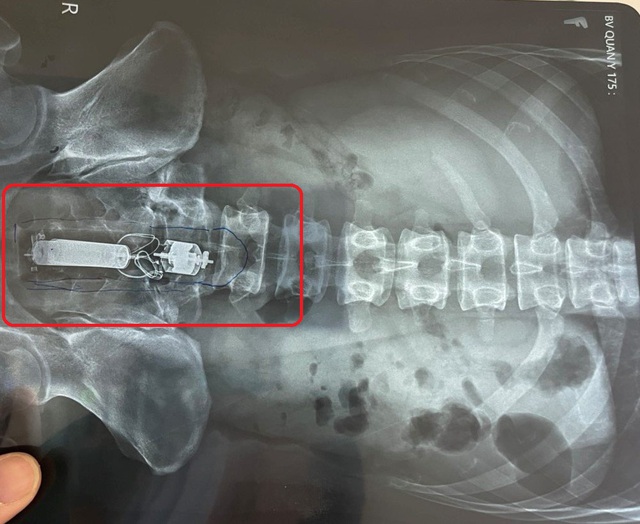

Hình ảnh kiểm tra cho thấy dương vật giả bị kẹt trong trực tràng của bệnh nhân